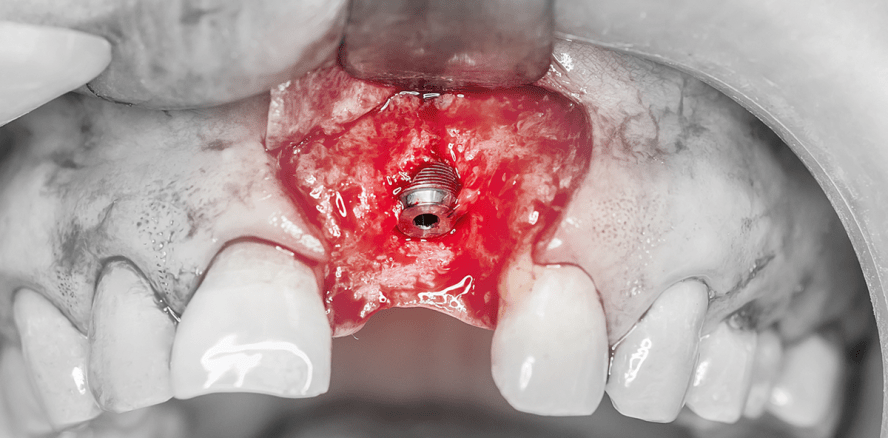

Nach dem Einheilen in die Knochenkavität werden Implantate beim Zweiphasensystem nach circa drei bis sechs Monaten freigelegt und der Zahnarzt kann mit der Herstellung der Suprakonstruktion beginnen. Bei der

Freilegung wird die Schleimhaut entfernt

und ein oder mehrere Aufbauelemente eingefügt. Die Freilegung stellt einen chirur

gischen Eingriff sehr unterschiedlichen Ausmaßes dar.